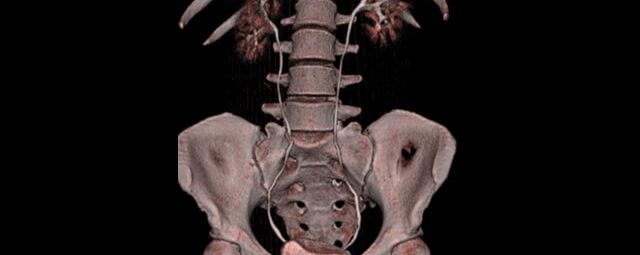

Ganz auf Patientensicherheit ausgelegt werden mit diesem CT individuell für jeden Patienten automatisch Strahlendosis und Kontrastmittelmenge reduziert und gleichzeitig bestmöglicher Bildkontrast und eine hohe Detailauflösung erreicht.

Spezielle Software ermöglicht jetzt zum Beispiel:

• verbesserte Bildqualität bei Patienten mit Implantaten (z. Bsp. Hüftendoprothesen)

• besonders hochauflösende, strahlendosissparende Darstellung aller Skelettstrukturen

• mehrdimensionale Darstellung vasculärer Strukturen mit zahlreichen Auswertungstools